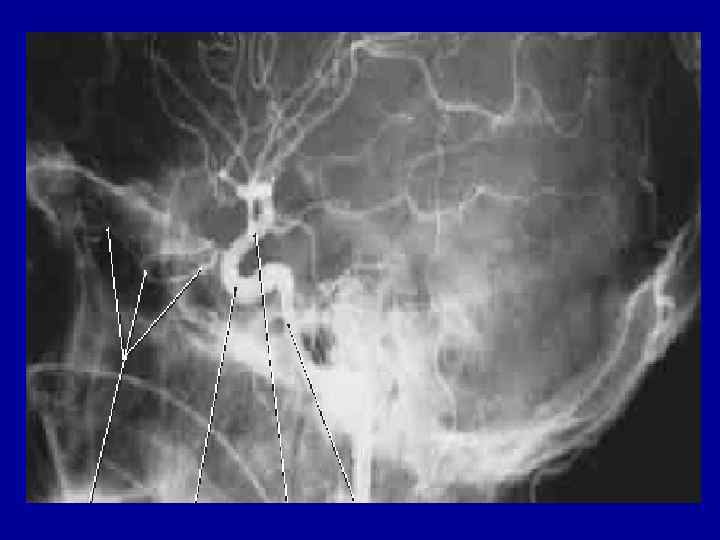

Методы изучения топографической анатомии 1. Послойное препарирование 2. Препарирование через окончатые разрезы 3. Наливки Методы изучения топографической анатомии 1. Послойное препарирование 2. Препарирование через окончатые разрезы 3. Наливки контрастными веществами 4. Методы прижизненного исследования: рентгеноскопия, УЗИ, компьютерная томография, термография и т. д.